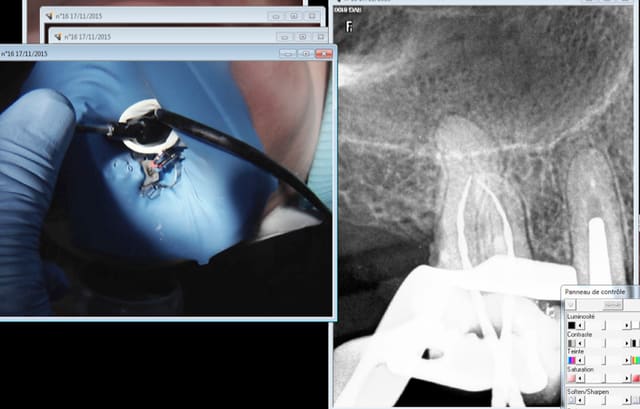

Capture d e cran 2015 11 17 12.11 - Eugenol

Radio ortho centrée sans digue et pour cause c'est une "auto radio" pas facile à faire sans angulateur pour positionner le long cone tout seul.

Sinon je peux essayer avec une digue pour voir. -))))

La 7 serait ardue à choper par contre.

Le capteur "pivote " sur l'axe de l'angulateur si on ne fait pas gaffe. curieux.